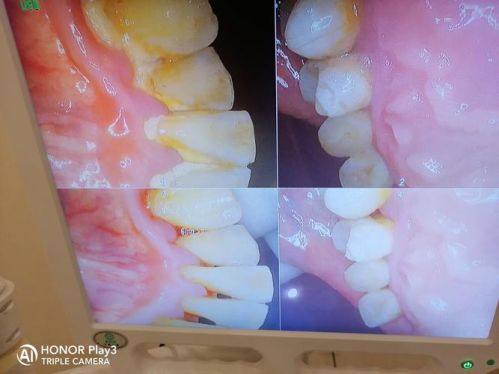

口腔颌面外科、牙槽疾病诊疗与早期种植修复:能够效率高处理各类口腔颌面外科病症与牙槽疾病,开展早期种植修复,帮助患者修复口腔正常功能与美观形态。